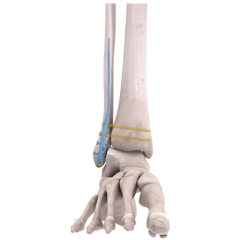

Explore our broad range ofOrthopedic Products

We are dedicated to improving the quality of life of patients suffering with bone and joint problems by delivering the latest medical devices that are proven to be effective and backed by scientific studies and research

• Surgical Devices